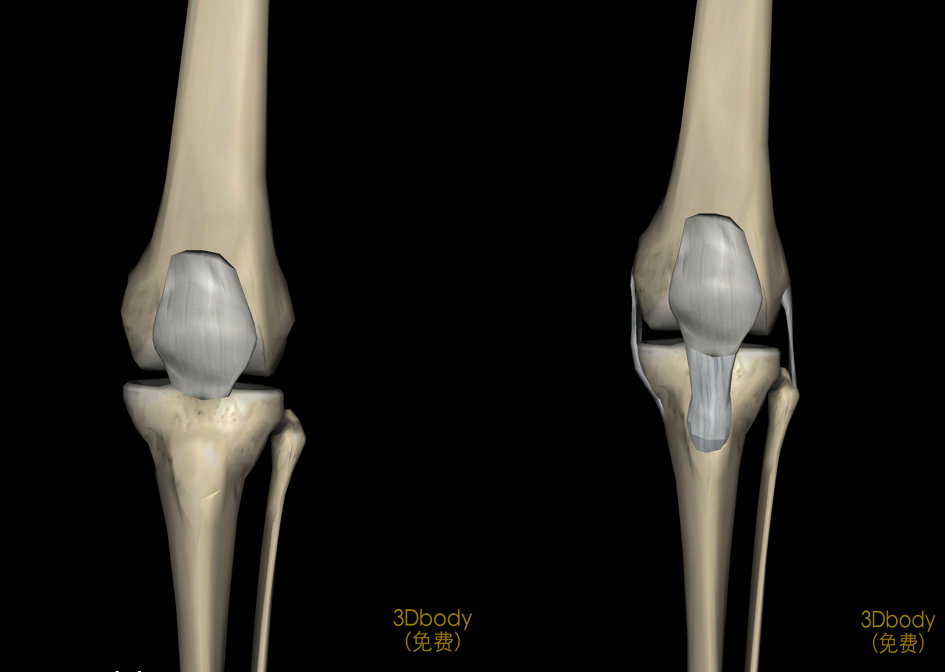

膝关节解剖

病因和发病机制关节的基本结构:关节面、关节软骨、关节腔、关节囊关节软骨:厚度约为2-7mm软骨表面光滑,摩擦系数很小,故有利于关节活动。